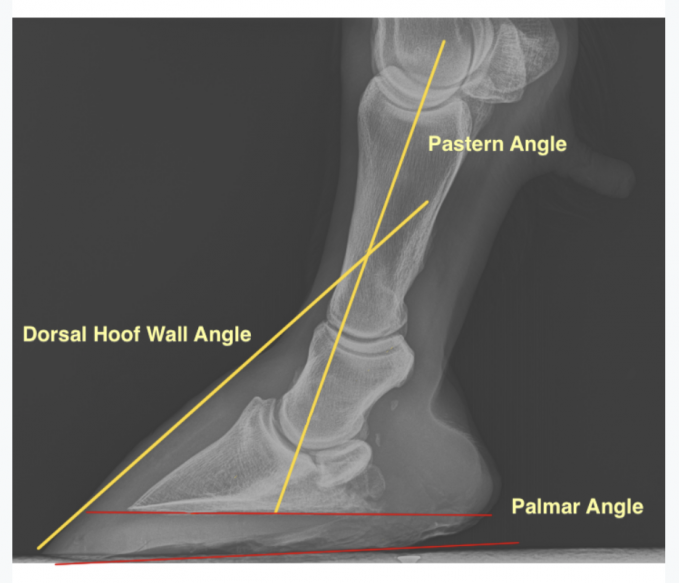

Hooves must be able to expand when they make contact with the ground, plus roll forward efficiently (good “rollover” requires toes to be properly shortened and beveled). The feet must be carefully balanced, with all weight-bearing structures brought into play. A skilled farrier should first remedy any pre-existing problems, including underrun, contracted, or sheared heels mismatched hoof angles or a broken hoof/pastern axis. Shelley PaulsonĬorrect trimming/shoeing should be the basis of all heel-pain treatment, with any medicinal or surgical strategies considered adjuncts. Though navicular syndrome usually can’t be fully cured, proper management and treatment can reduce stress, inflammation, and pain in the affected areas, and some horses may even remain ridable.

The intermittent use of NSAIDs (such as bute) may also be a part of the plan. In addition, depending on the source of your horse’s pain, your vet may propose medical therapies applied systemically or injected into the coffin joint or navicular bursa to reduce inflammation or preserve bone (at right). If your horse does develop heel pain, your vet is likely to recommend therapeutic trimming and/or shoeing (see below). These include correct and regular hoof care, proper nutrition (that prevents obesity), regular exercise plus turnout, and decent footing. To lower the risk that your horse will ever develop navicular syndrome, provide all the horsekeeping standards that are basic to excellent care. MRI and other advanced imaging techniques may be needed the more precise the diagnosis of the cause, the more precise and effective the treatment. Your vet will determine whether your horse has navicular syndrome, then try to pinpoint which disease process is at work. Watch for these symptoms and consult with your veterinarian if any appear: increased stumbling a shortened, choppy stride standing with a front foot pointed front-end tenderness on hard ground or when moving in a circle. Horses with large, heavy bodies and small hooves are at even greater risk. Heel pain can occur to any horse, but the risk is higher for Quarter Horses, Thoroughbreds, and warmbloods, especially those over the age of 7. Palmar heel pain is an alternate term, referring to the site of the nerve block (at the back and bottom of the front feet) that resolves pain for all these conditions.